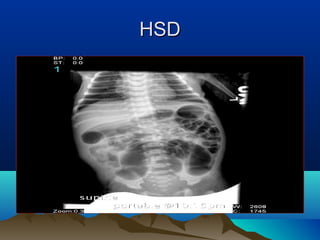

• Abdominal plain X-rays

Abdominal X-ray (HSD)Abdominal X-ray (HSD)

HSDHSD

• #75 Dilated small and large bowel loops, prominent transverse, descending, sigmoid